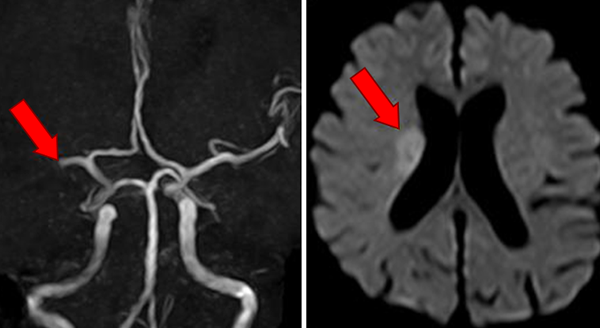

脳梗塞

脳の血管が詰まってしまい、詰まった箇所の先に血液が供給されなくなってしまうのが脳梗塞です。そして閉塞を来たした場所に対応して、様々な症状が引き起こされます。半身の麻痺や言葉の障害などが、その代表例です。半身が麻痺となりますと、食事、排泄、入浴といった、これまでは当たり前の日常生活を一人では行えなくなります。発症した時点から突然、一人では何もできなくなってしまい、介護を受ける人生が待っています。

日本人において、糖尿病の患者さんが脳梗塞となるリスクは男性で2.2倍、女性では3.6倍にもなることが分かっています。脳梗塞は、加齢、高血圧、糖尿病、脂質異常症、慢性腎臓病、運動不足、喫煙、肥満、家族歴、などが危険因子となりますが、その中でも特に「糖尿病」と「高血圧」が組み合わさると高率に発症してしまいますので、きちんとした管理で予防を心掛けることが重要です。

右中大脳動脈が閉塞しています。梗塞の程度により症状はさまざまですが何らかの介護なしでは生活できないことがほとんどです。

つまりそうならないように事前に管理を行う(=血糖管理を中心とした危険因子の是正)が重要なのです。